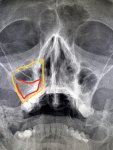

>>327476174

Левую гайморову залепило.

Гайморит слева (пристеночное утолщение слизистой) и вставные зубы

Аноним 09/12/25 Втр 08:27:51 #47 №327475609

Скинь серце или блять желудок штоли нахуй эти кости ебаные